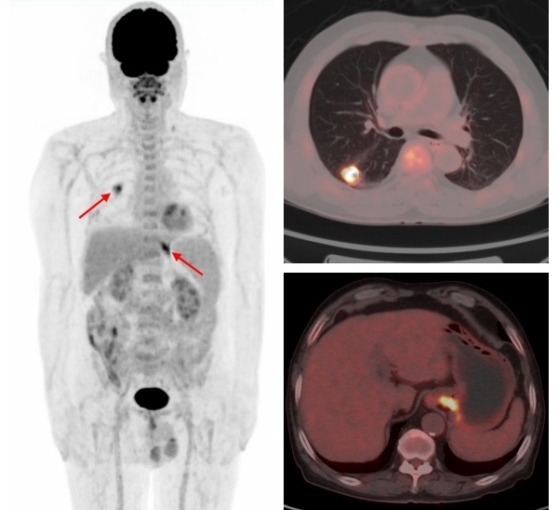

例1:中年男性,CT發(fā)現(xiàn)右肺上葉結(jié)節(jié),1.1cm×1.0cm,余未見異常,這時候患者初步分期應(yīng)該是ⅠA期,屬于早期肺癌,可以行根治性手術(shù)。而PET/CT檢查示:肝臟、多發(fā)骨骼轉(zhuǎn)移,這時候分期直接跳到ⅣB期,屬于晚期肺癌,不適合手術(shù),可以根據(jù)病理、基因檢測結(jié)果選擇合適的藥物治療或聯(lián)合治療方案,避免了無效的手術(shù)創(chuàng)傷。病理:浸潤性腺癌。

原發(fā)肺腺癌合并賁門腺癌